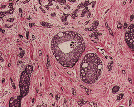

Histoquímica

Técnica que, através de reações químicas, permite evidenciar determinados constituintes celulares, depósitos exógenos e microorganismos.

Imunocitoquímica

É uma técnica que permite identificar componentes celulares específicos através de reações antigénio-anticorpo. É importante para o completo diagnóstico anatomopatológico, bem como para orientação terapêutica.